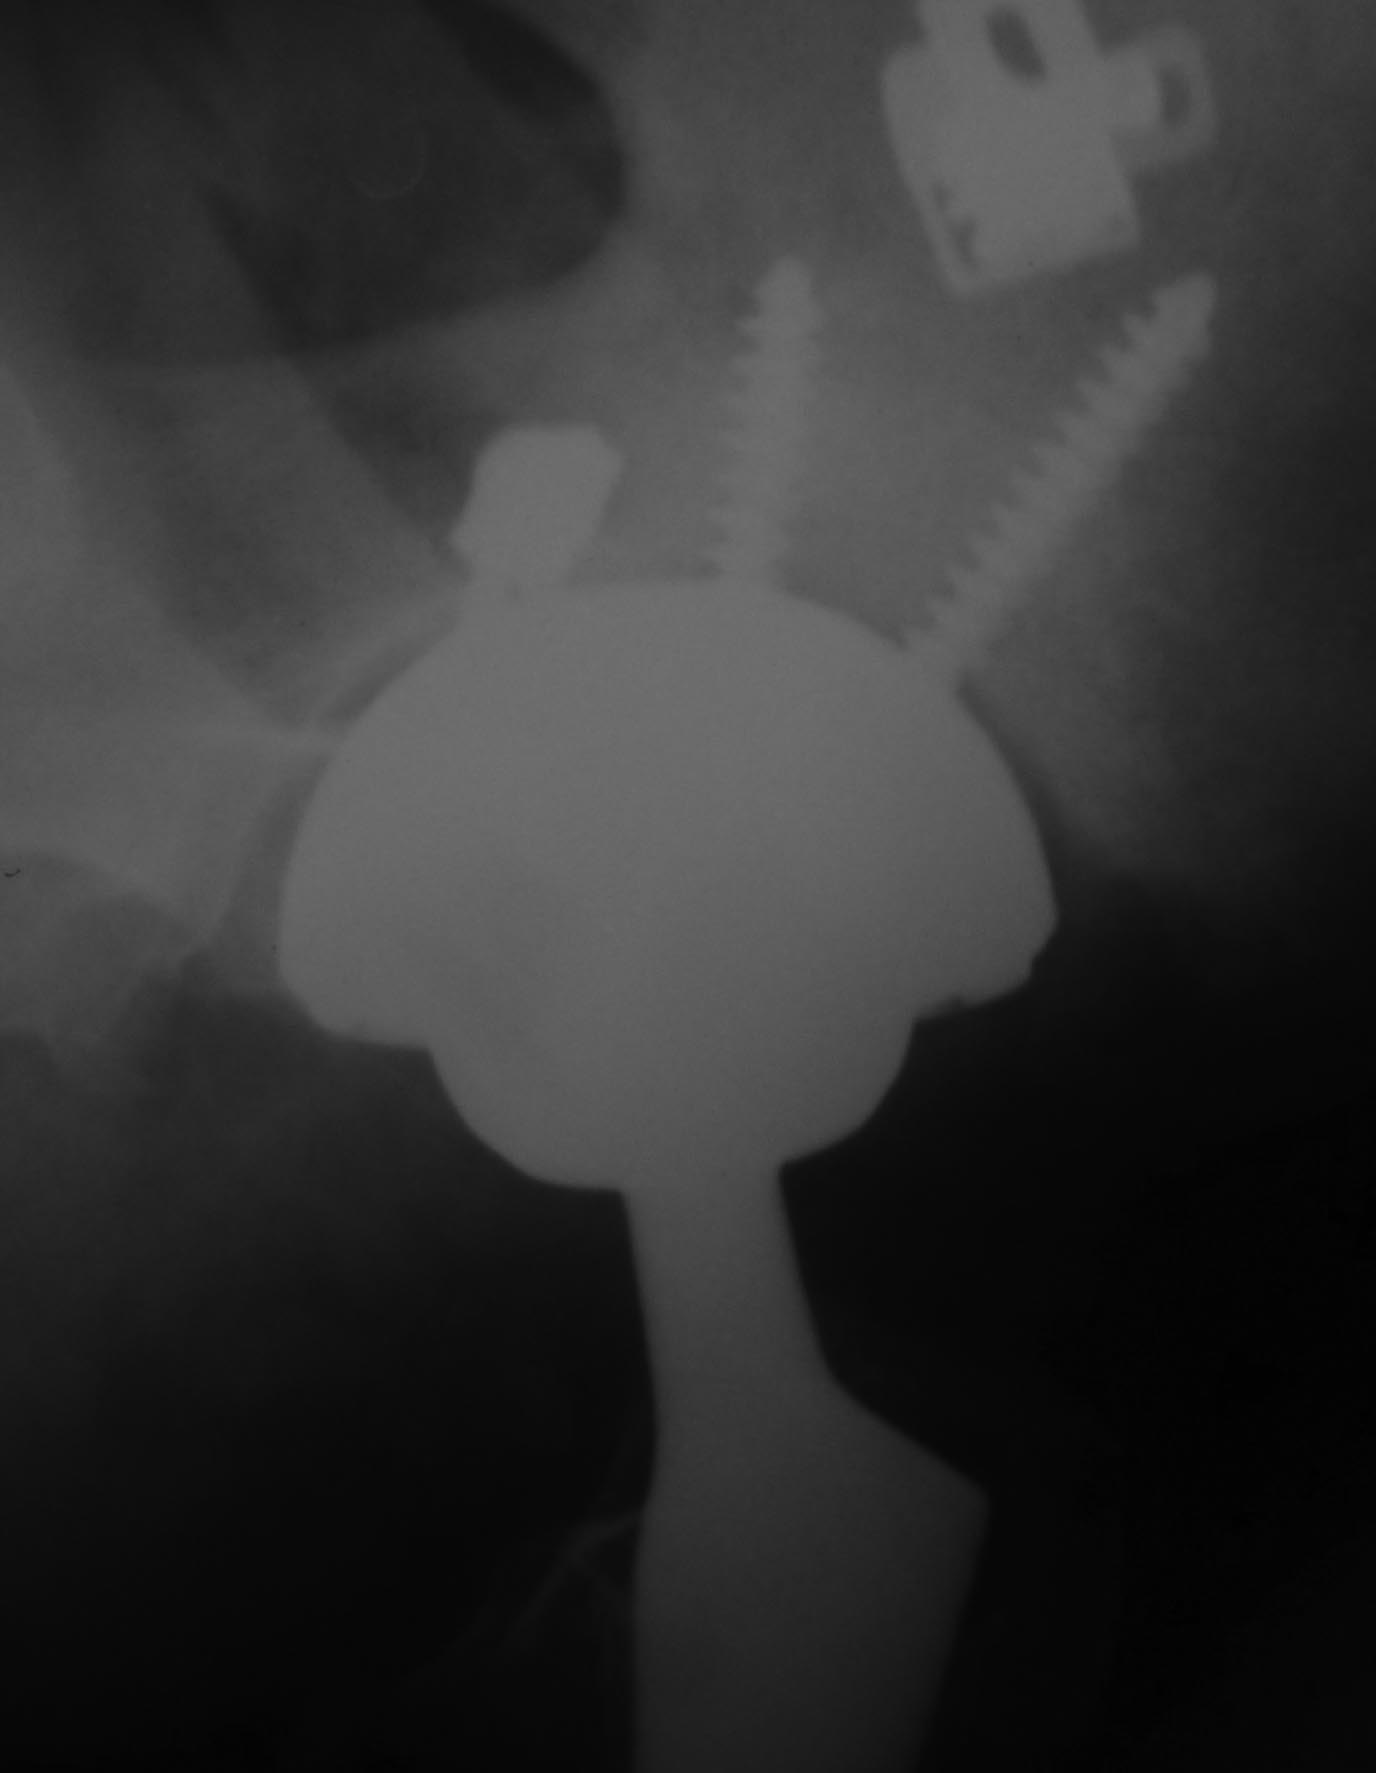

Пациент 58 лет оперирован 10 лет назад по поводу вывиха правого бедра с переломом головки. Во время открытого вправления был поврежден седалищный нерв (ягодичный доступ), по поводу чего впоследствии выполнены 3 вмешательства с неполным положительным эффектом. Через несколько месяцев после открытого вправления было осуществлено тотальное эндопротезирование.

Сейчас больше всего беспокоит стартовая боль, ходит с тростью, опираясь на нее 2 руками, ежедневно принимает нимесулид, хотя пытается убедить себя и окружающих, что, кроме стартовых, других болей нет. Резко ограничены движения в правом тазобедренном суставе, попытка ротации болезненна до крика. У невролога был - неврологическая патология отвергнута. Анализы крови нормальные, лихорадки нет. Казалось бы имеются все признаки нестабильности тазового компонента эндопротеза.

Вопрос: возможна ли нестабильность без рентгенологических признаков разрежения костной ткани вокруг винтов?

Уважаемый Сергей, у пациента имеются и клинические и рентгенологические признаки нестабильности чашки. Отсутствие резорбции вокруг винтов не должно Вас смущать. Ревизионное вмешательство однозначно показано.

Скорее всего нужно говорить о нестабильности вертлужного компонента. Есть разряжение вокруг чашки, которая скорее всего держится за счет винтов. Реэндоротезирование с заменой вертлужного компонента. Но перед операцией добиться получения пунктата на бакпосев, лучше даже 2 или 3 раза. Если есть инфекция то двухэтапное реэндопротезирование с применением цементного спейсора.

если винты сломаны на уровне чашки

Можно было начать с обычной рентгенограммы таза и простым анализом крови. Вместо КТ срезов, нужна прямая рентгенограмма таза, которая позволит сравнить уровень суставов и увидеть расшатывание вокруг ацетабулярного, а также бедренного компонентов. Сфокусированные КТ срезы, особенно 3Д не позволяют распознать вовлечение на уровне бедра и оценить артропластику в целом!

Спасибо за развернутый ответ. Но по поводу данного больного я задал единственный конкретный интересующий меня вопрос: возможна ли нестабильность вертлужного компонента при отсутствии признаков нестабильности фиксирующих чашку винтов? И именно для возможности ответить на этот вопрос представлены 3D срезы, позволяющие точнее оценить расположение винтов.К сожалению, на интересующий меня вопрос вы не ответили. А про результаты обычных анализов крови я написал, они в пределах нормы. И обычные рентгенограммы таза с захватом обеих ног пациенту сделаны. К ним у меня нет вопросов.